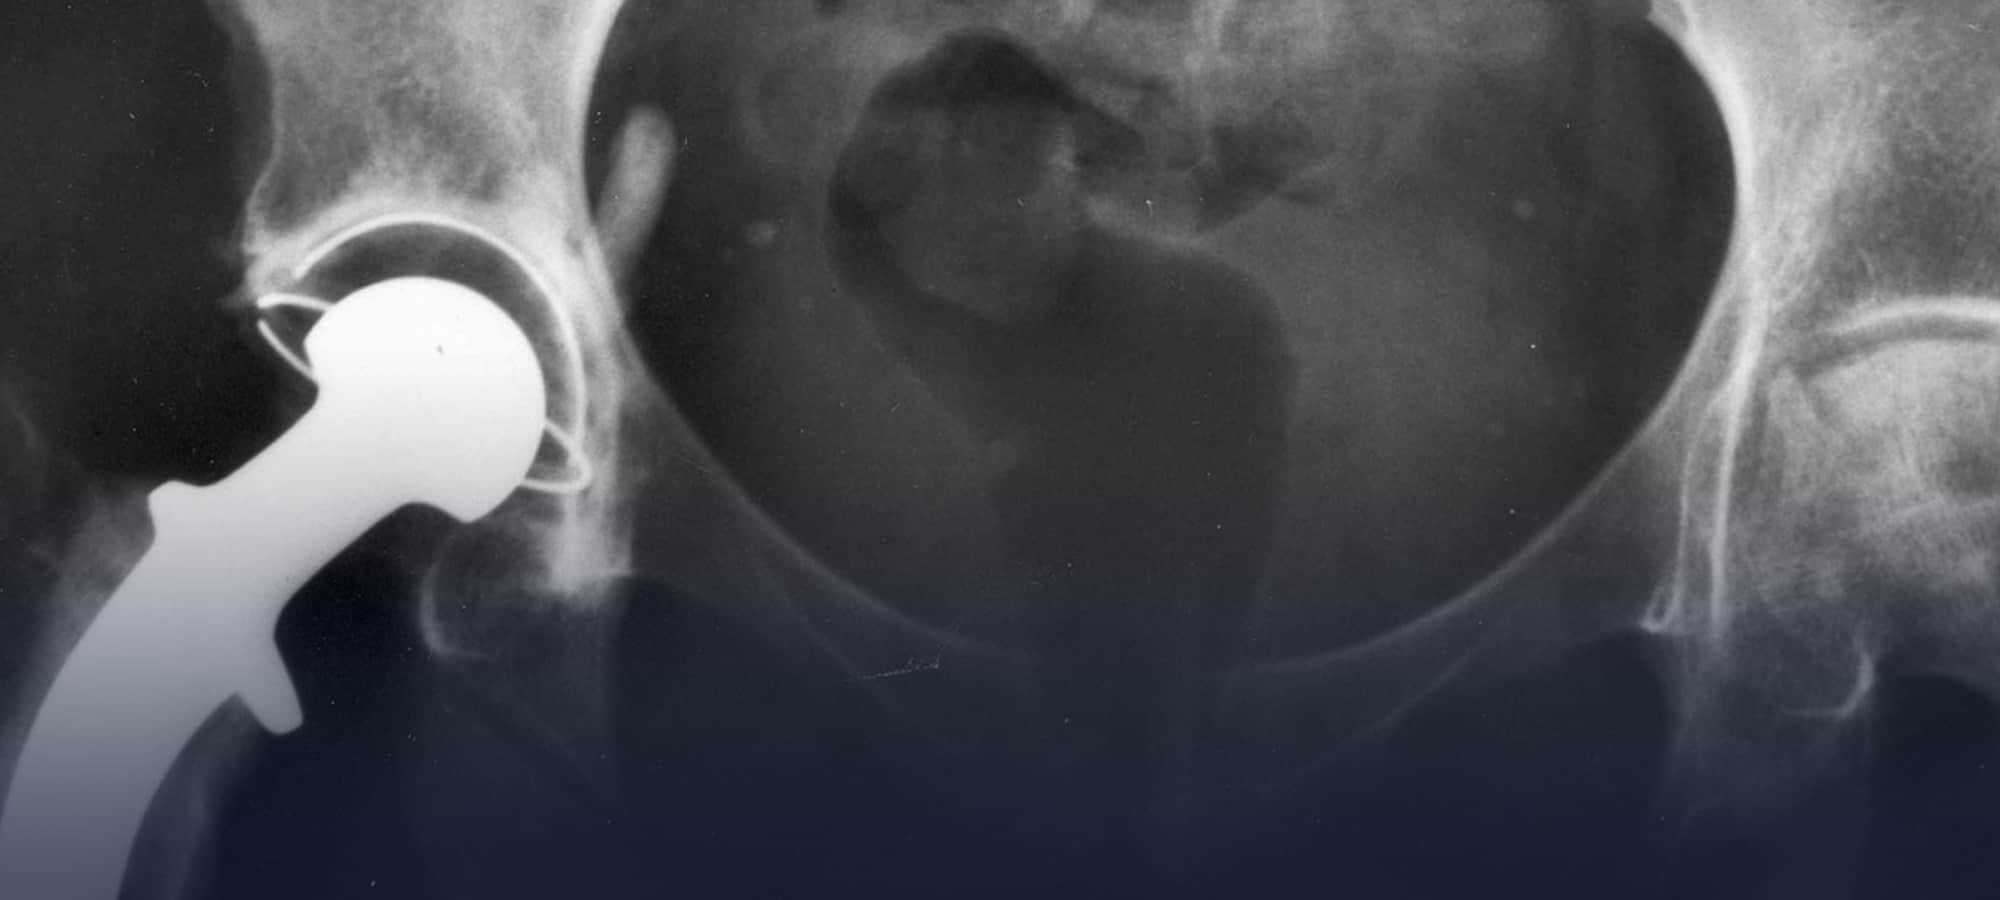

Artificial hip manufacturer Stryker Orthopaedics has notified surgeons that it is voluntarily recalling certain lots and sizes of its LFIT Anatomic COCR V40 Femoral Heads because of serious health risks to patients. Many people who received this hip replacement system have been experiencing great pain as well as toxic levels of cobalt and chromium in their bodies. A second hip revision surgery is needed to remove these devices because of the serious flaws in their design.

LFIT Anatomic CoCr V40 femoral heads are modular components used in total hip replacement procedures.

It has been identified that some LFIT Anatomic CoCr V40 femoral heads manufactured before 2011 have a higher than expected incidence of taper lock failures. The taper lock is the part of the implant that connects the femoral head to the femoral neck.